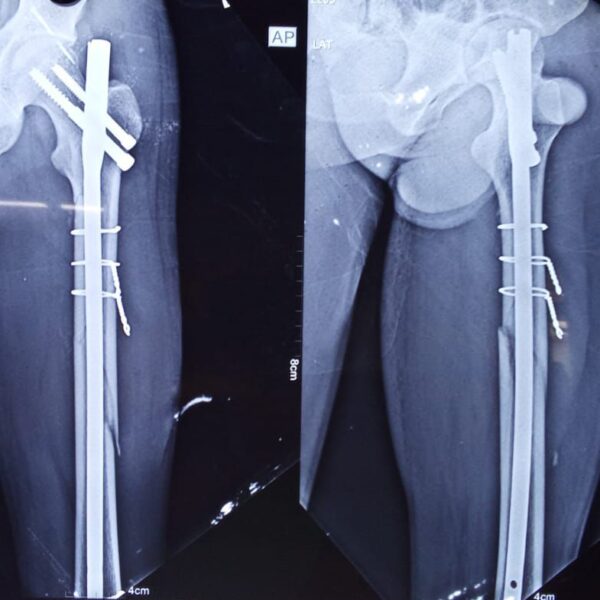

Moments That Mark Meaningful Recovery

Witness real patient transformations at The Ortho Clinic through images that reflect successful treatments and restored mobility.